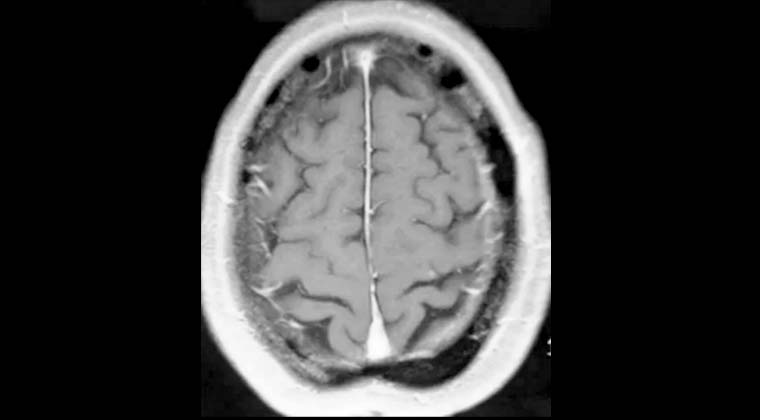

Жалобы: слабость в левой стороне тела, нарушение походки в течение 2 недель. Диагноз: множественные метастазы рака легких в головной мозг.

Рисунок 1: 25.02.2022 Планирование лечения Гамма-ножом опухоли в правой лобной доле, выраженный перифокальный отёк.

Рисунок 2: 25.02.2022 Одновременно проведено лечение Гамма-ножом опухоли в левой височной доле.

Рисунок 3: 25.07.2022, через 5 месяцев после лечения контрольное МРТ показало, что опухоль в правой лобной доле исчезла, пациентка ходит самостоятельно.

Рисунок 4: 25.07.2022, контрольная МРТ показывает, что опухоль в левой височной доле также исчезла.